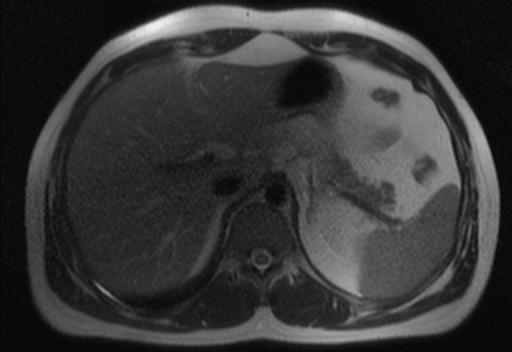

Методы динамического контрастирования печени на МРТ

Раздел: Снимки-подсказки